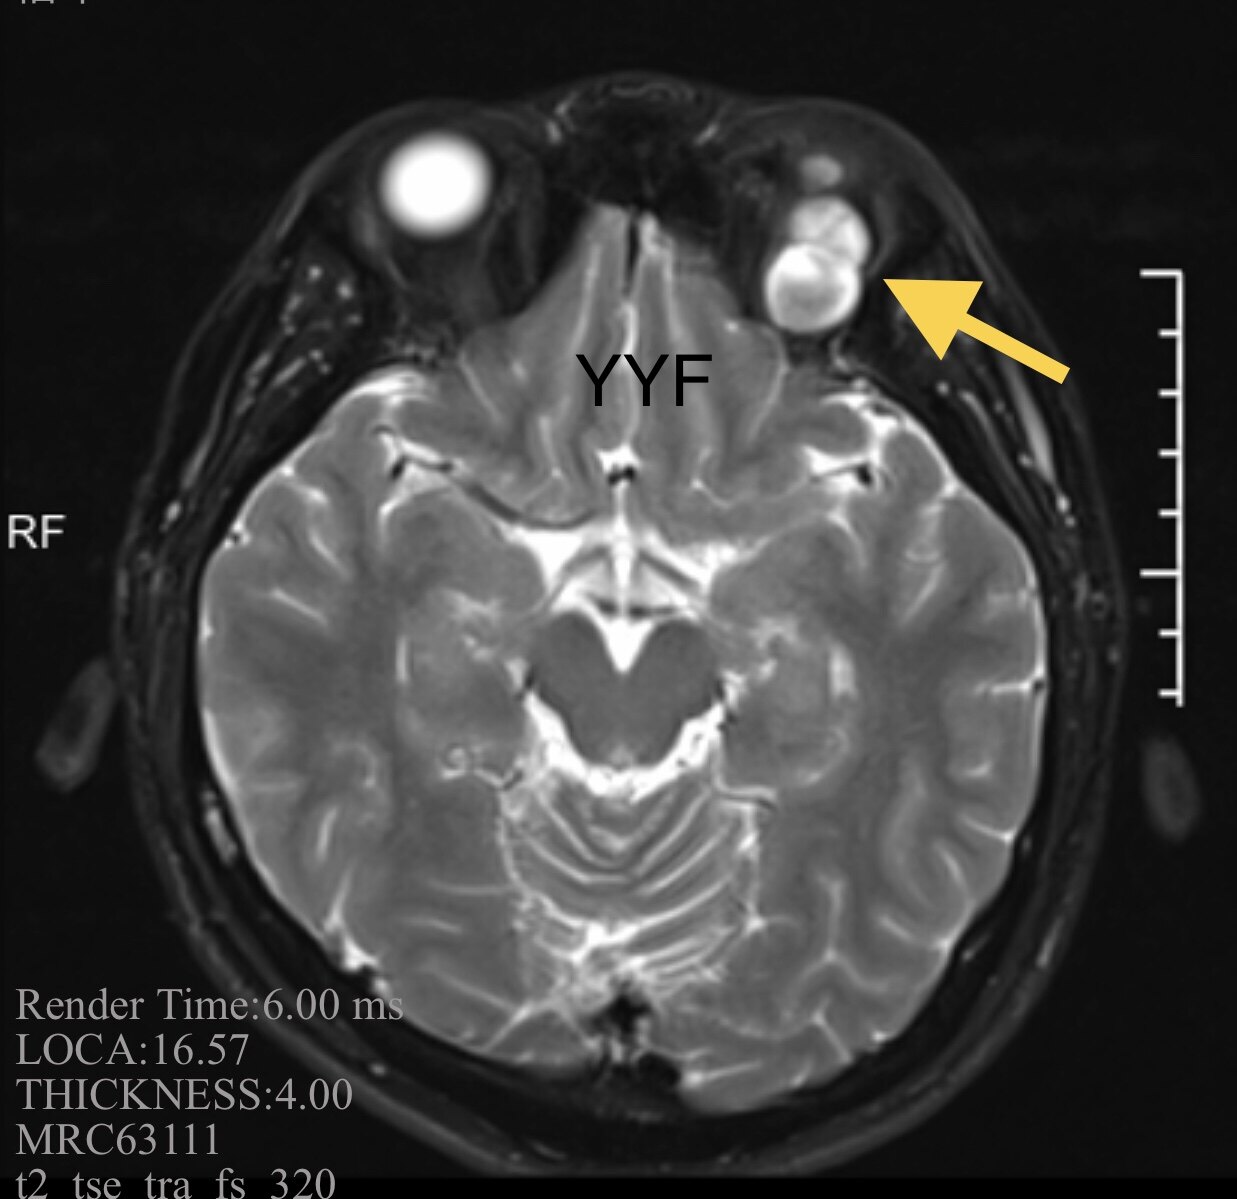

影像学显示肿物呈现不规则、结节状。

根据T2加权上的特殊表现首先考虑神经鞘瘤,其形态符合神经起源的肿瘤。

T2加权表现有特征性